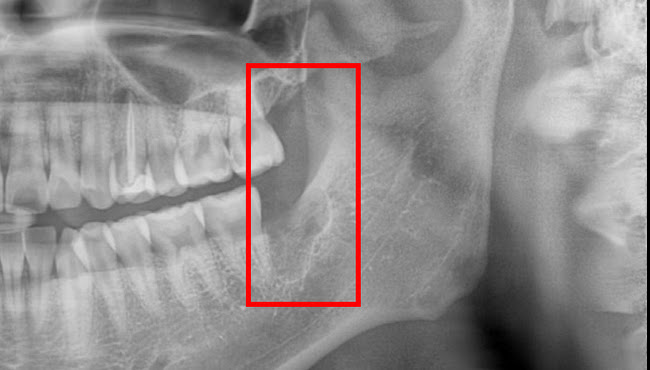

사랑니는

건강한 구강관리를 위해 발치하는 것을 추천드립니다

치아에 통증이 없거나 관리가 잘 된다면 발치할 필요는 없습니다.

하지만 사랑니는 구강 내 가장 깊숙한 곳에 위치하고 있으며,

칫솔질이 잘 되지 않아 잇몸에 염증이 생기는 경우가 많습니다.

종종 앞쪽 치아를 썩게 만들며, 기능적인 활용도가 낮아 발치하는 것이 구강건강에 좋습니다.